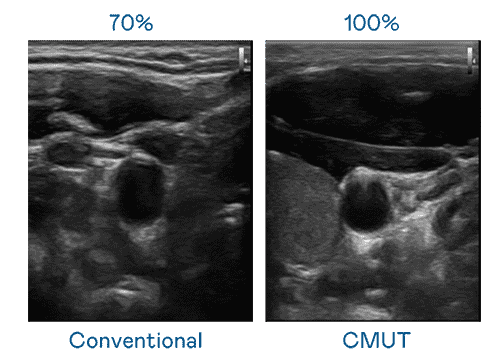

CMUT 技术是一种用电容式微机电元件来产生超音波讯号的技术。。。与传统 PZT 压电式技术相比,,,,CMUT 频宽增加 30%,,更宽频的超音波讯号让影像解析度大幅提升,,是实现高影像品质医疗超音波扫描、、促进精准医疗发展的关键技术。。。

大频宽带来超清晰影像

超音波影像的解析度高低,,,,首先取决于探头能发出的讯号频宽。。。红龙扑克 CMUT 可提供高清晰的超音波讯号,,提供高频宽、、、、高灵敏度、、影像纹理细节更高的超音波影像,,,,协助医护人员缩短影像判读时间及利用精准的医疗影像进行诊断。。。。